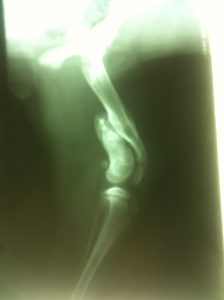

Vale x-ray